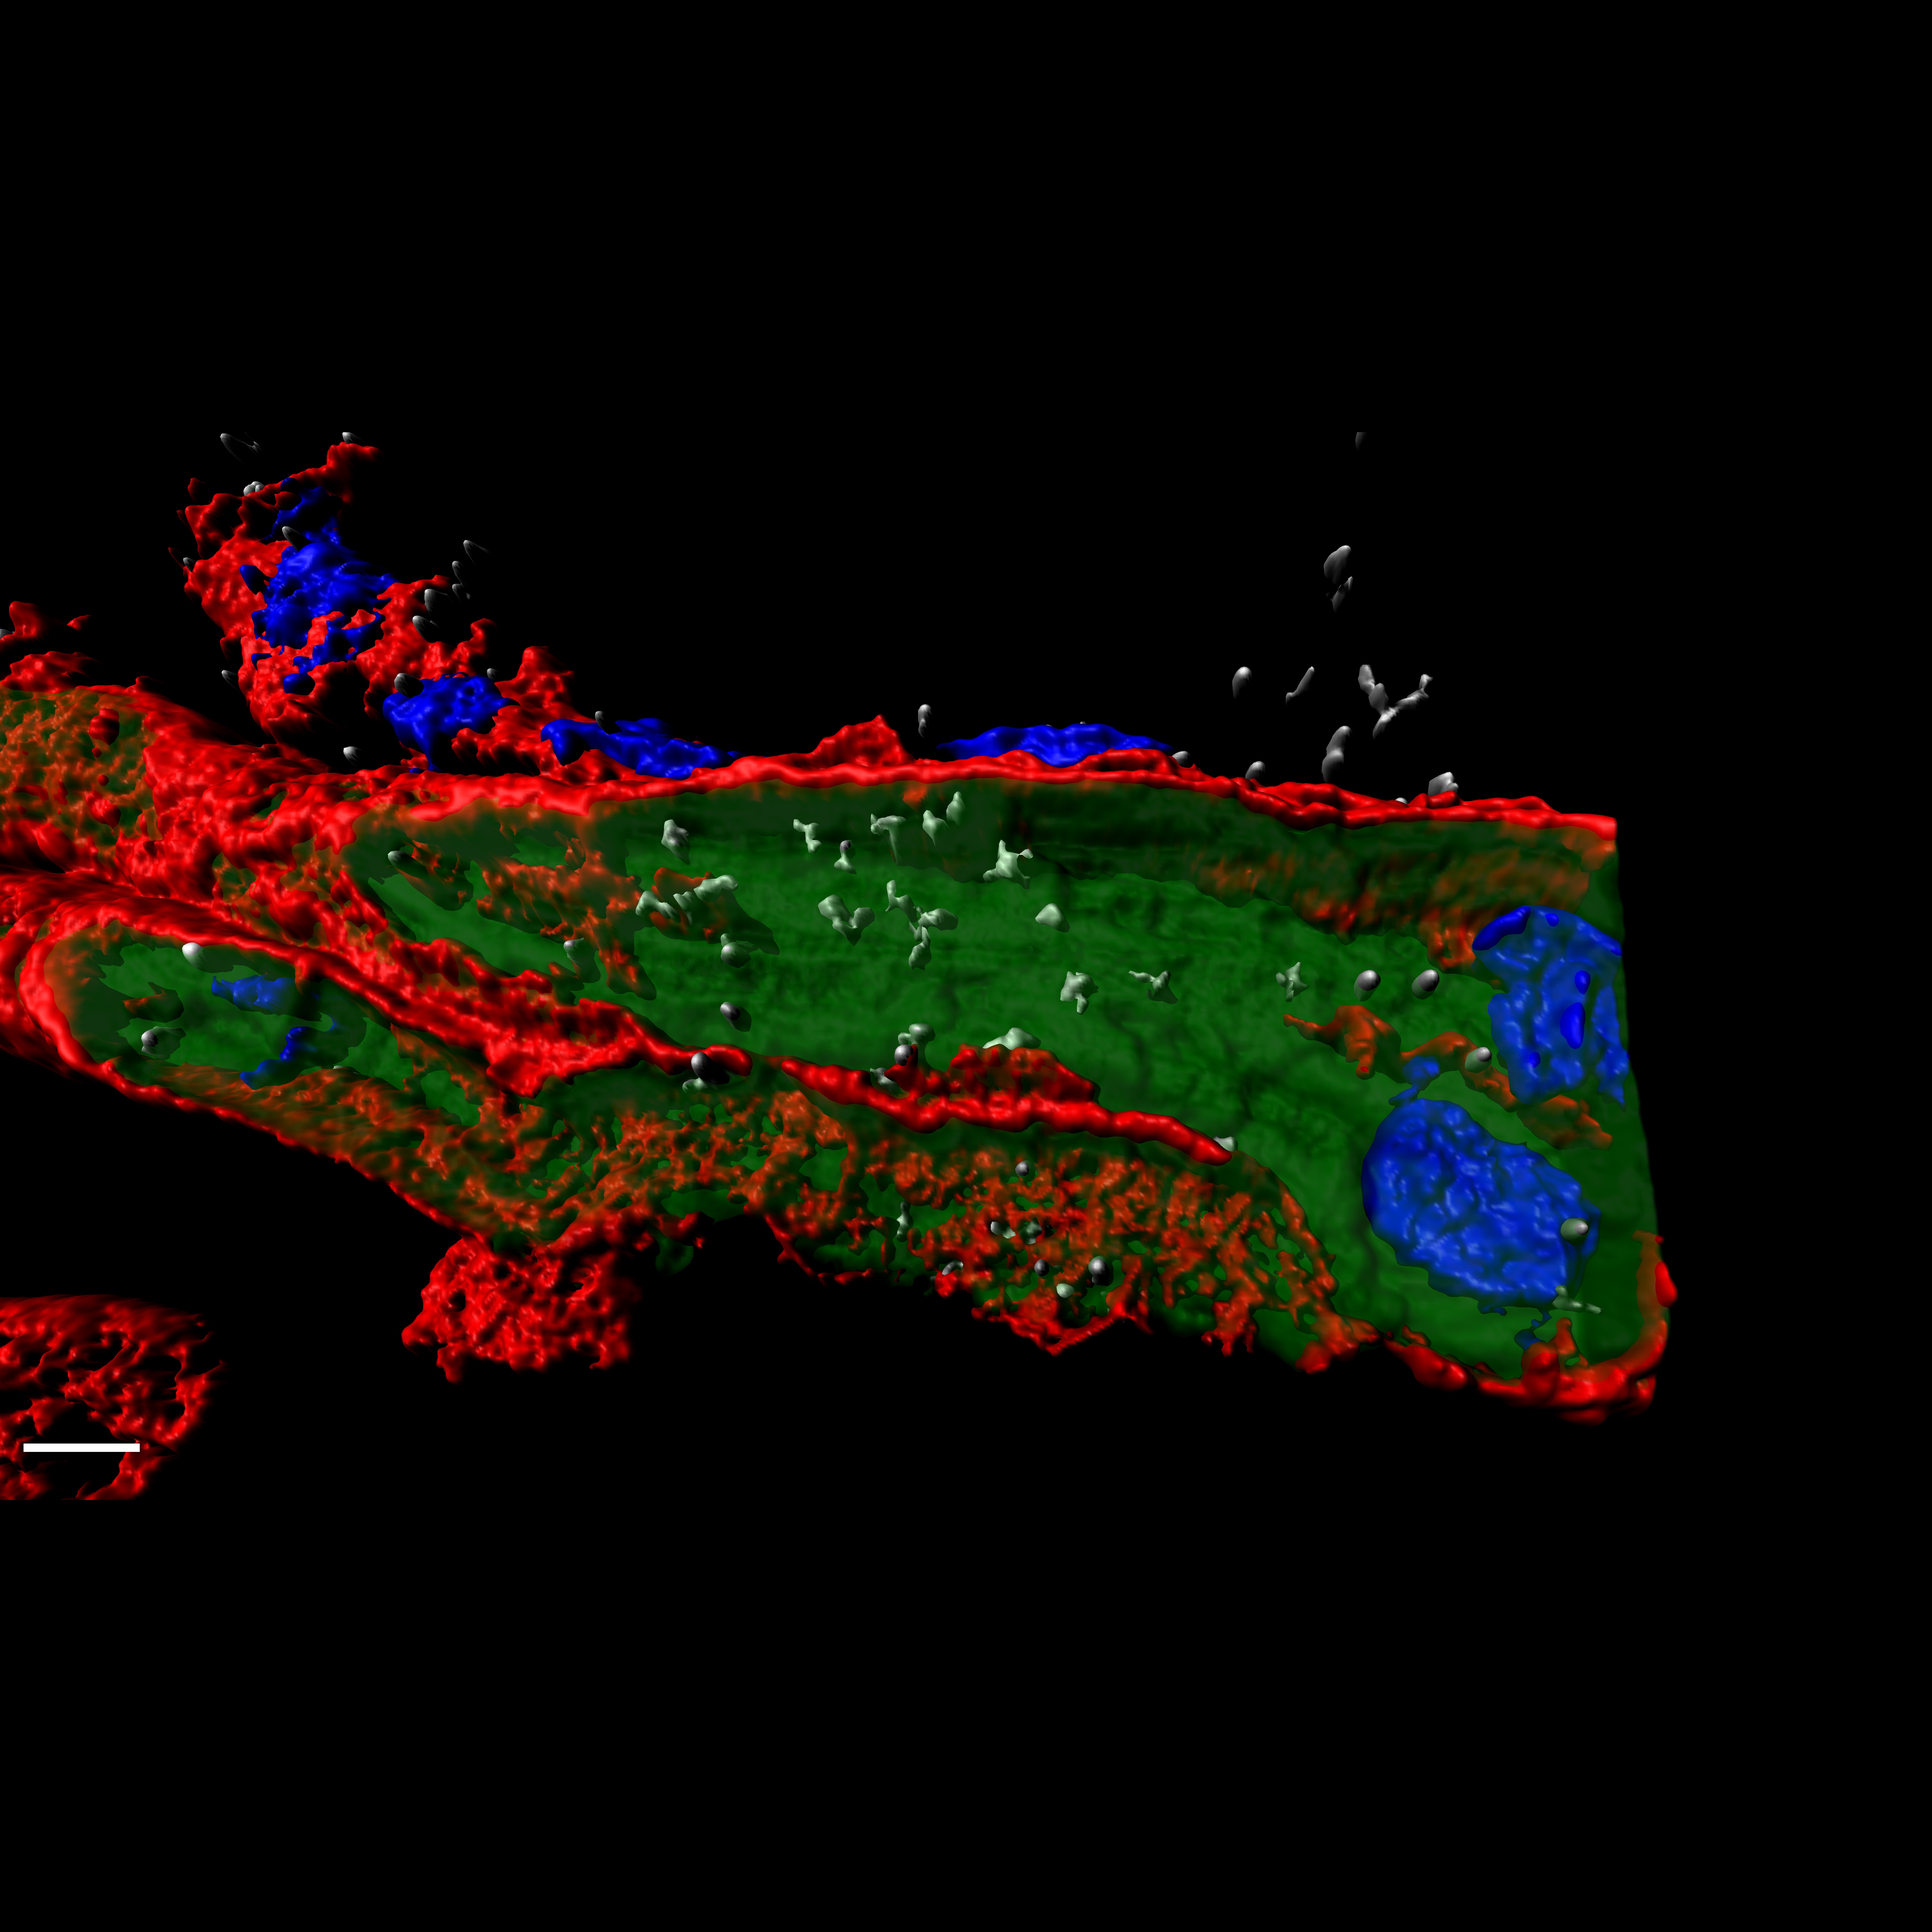

• CIBERONC

Desarrollada una nueva terapia prometedora contra uno de los cánceres de mama más agresivos

04/05/2020